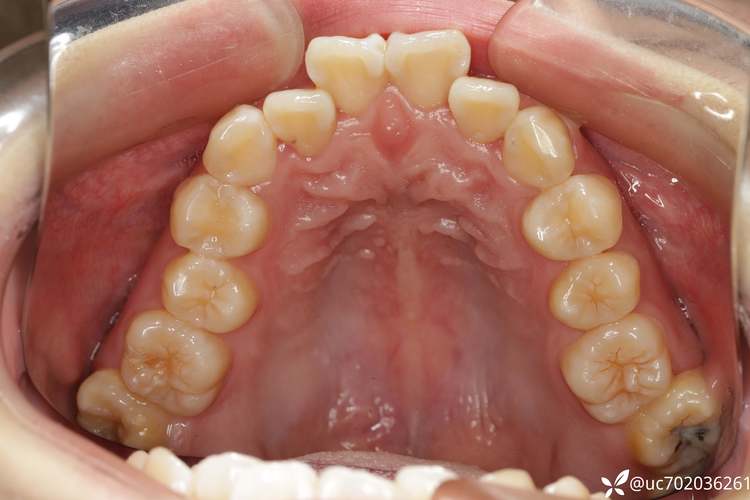

(图片来源网络,侵删) - 牙弓形态与对称性: